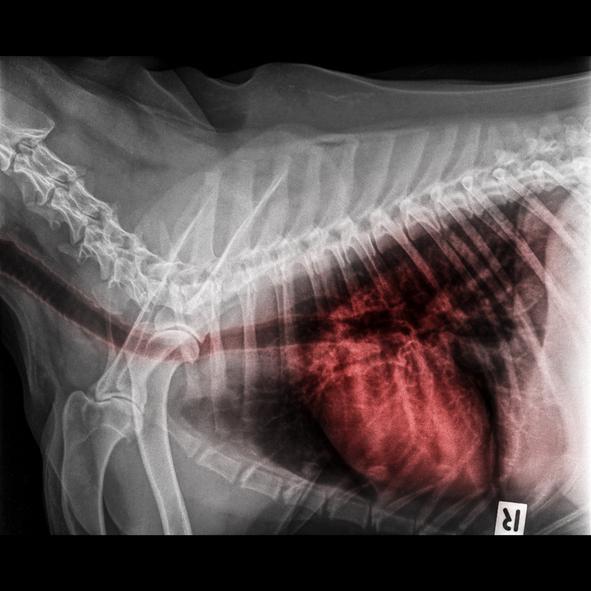

Exceto quando sabemos claramente qual é a causa da tosse, por exemplo, a presença de fumaça, caso em que teríamos que eliminar a causa desencadeante, ou uma coleira muito apertada que somente teríamos que afrouxar, se o seu cachorro tem tosse seca e engasgado você deverá contatar o veterinário. Principalmente, não utilize antitussígenos (xaropes) por sua própria conta. Somente este profissional pode examinar o cachorro e realizar os exames pertinentes para encontrar a causa. Pode ser necessário fazer uma radiografia torácica, ou em casos crônicos, uma lavagem intratraqueal. E é muito importante chegar ao diagnóstico, já que disto dependerá o tratamento.